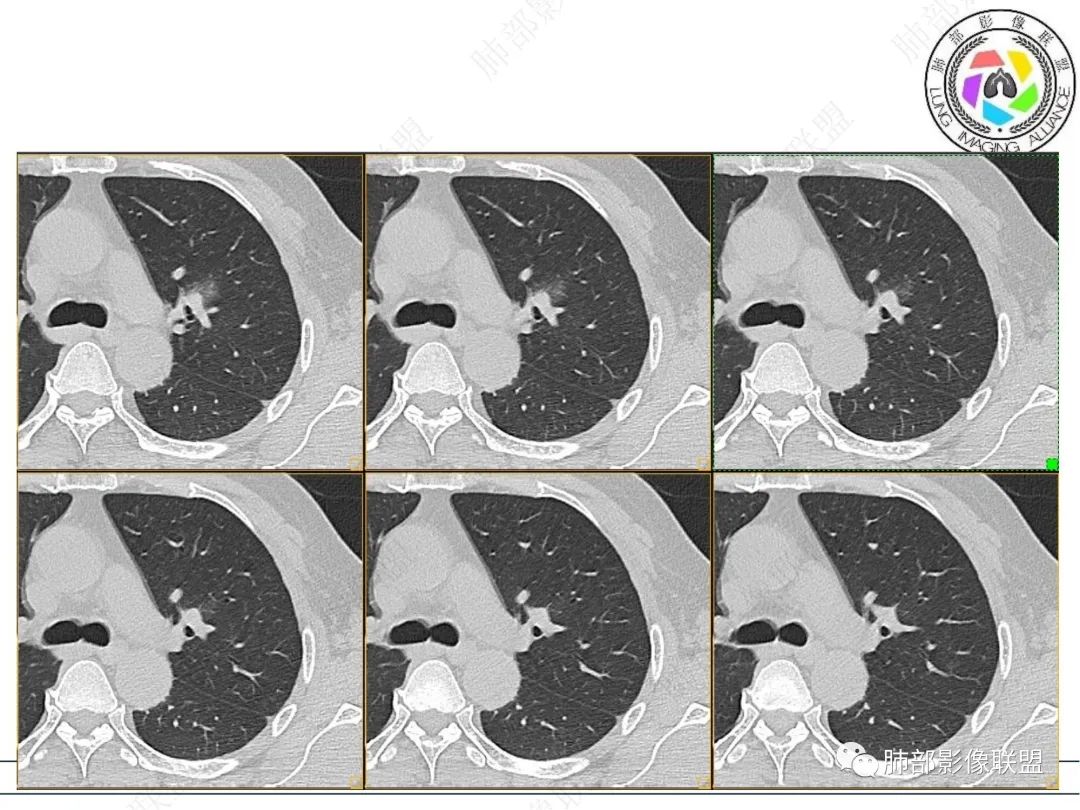

男性,肺结节3年,发现逐渐增大,影像表现,左肺舌段结节,边缘可见磨玻璃密度影,内部走形下舌段支气管变窄,增强呈持续强化,首先考虑肺腺癌,鉴别炎性肉芽肿,真菌/隐球菌。

中老年男性,发现结节,影像表现,左肺上叶结节,实性部分有膨胀性生长,边缘可见磨玻璃影,似清晰似不清晰,病灶与支气管关系密切,部分支气管似狭窄及僵硬,增强病灶强化明显,考虑腺癌(粘液性腺癌)鉴别炎性肉芽肿。

左肺上叶尖段支气管旁结节伴磨玻璃影,磨玻璃影边缘模糊,支气管走形正常,病变无明显分叶及毛刺,收缩不明显,增强呈延迟高强化。先考虑炎性肉芽肿。肿瘤待排。

左肺上叶支气管旁结节伴磨玻璃影,磨玻璃边缘略模糊,沿支气管走行,明显不均匀延迟强化,3年逐渐增大,考虑腺癌,鉴别淋巴增殖病变,炎性肉芽肿

中年男性,查体发现,左肺上叶靠近支气管旁实性结节,周围有磨玻璃影,边界清,密度高,明显强化,三年缓慢进展,考虑腺癌,鉴别类癌或炎性肉芽肿。

中年男性,体检发现左上肺结节,影像:左上肺欠规则结节+磨玻璃(边界欠清),沿支气管爬行生长,支气管无受累,增强后明显渐进性强化,3年随访增大,考虑低度恶性肿瘤,如淋巴增殖性病变,如淋巴瘤样肉芽肿可能。

中年男性,体检发现左肺上叶结节,三年逐渐长大,CT见左肺上叶部分实性结节,膨胀性生长,边缘边界清晰磨玻璃影,部分支气管狭窄,增强病灶强化明显。考虑恶性,腺癌可能。

中老年男性,左肺上叶中轴区实性结节及周围磨玻璃影,磨玻璃边界似清非清,关键点2019.10-2021.10-2022.05结节持续增大,增强后明显强化。考虑恶性结节可能大,腺癌(黏液腺癌)?鉴别炎性结节。

361度:

中年男性,无明显不适,左肺上叶前段支气管周围结节,复查逐渐增大,部分膨隆,边缘磨玻璃影内血管影增粗,复查亚段支气管阻塞,不均匀强化,考虑腺癌。